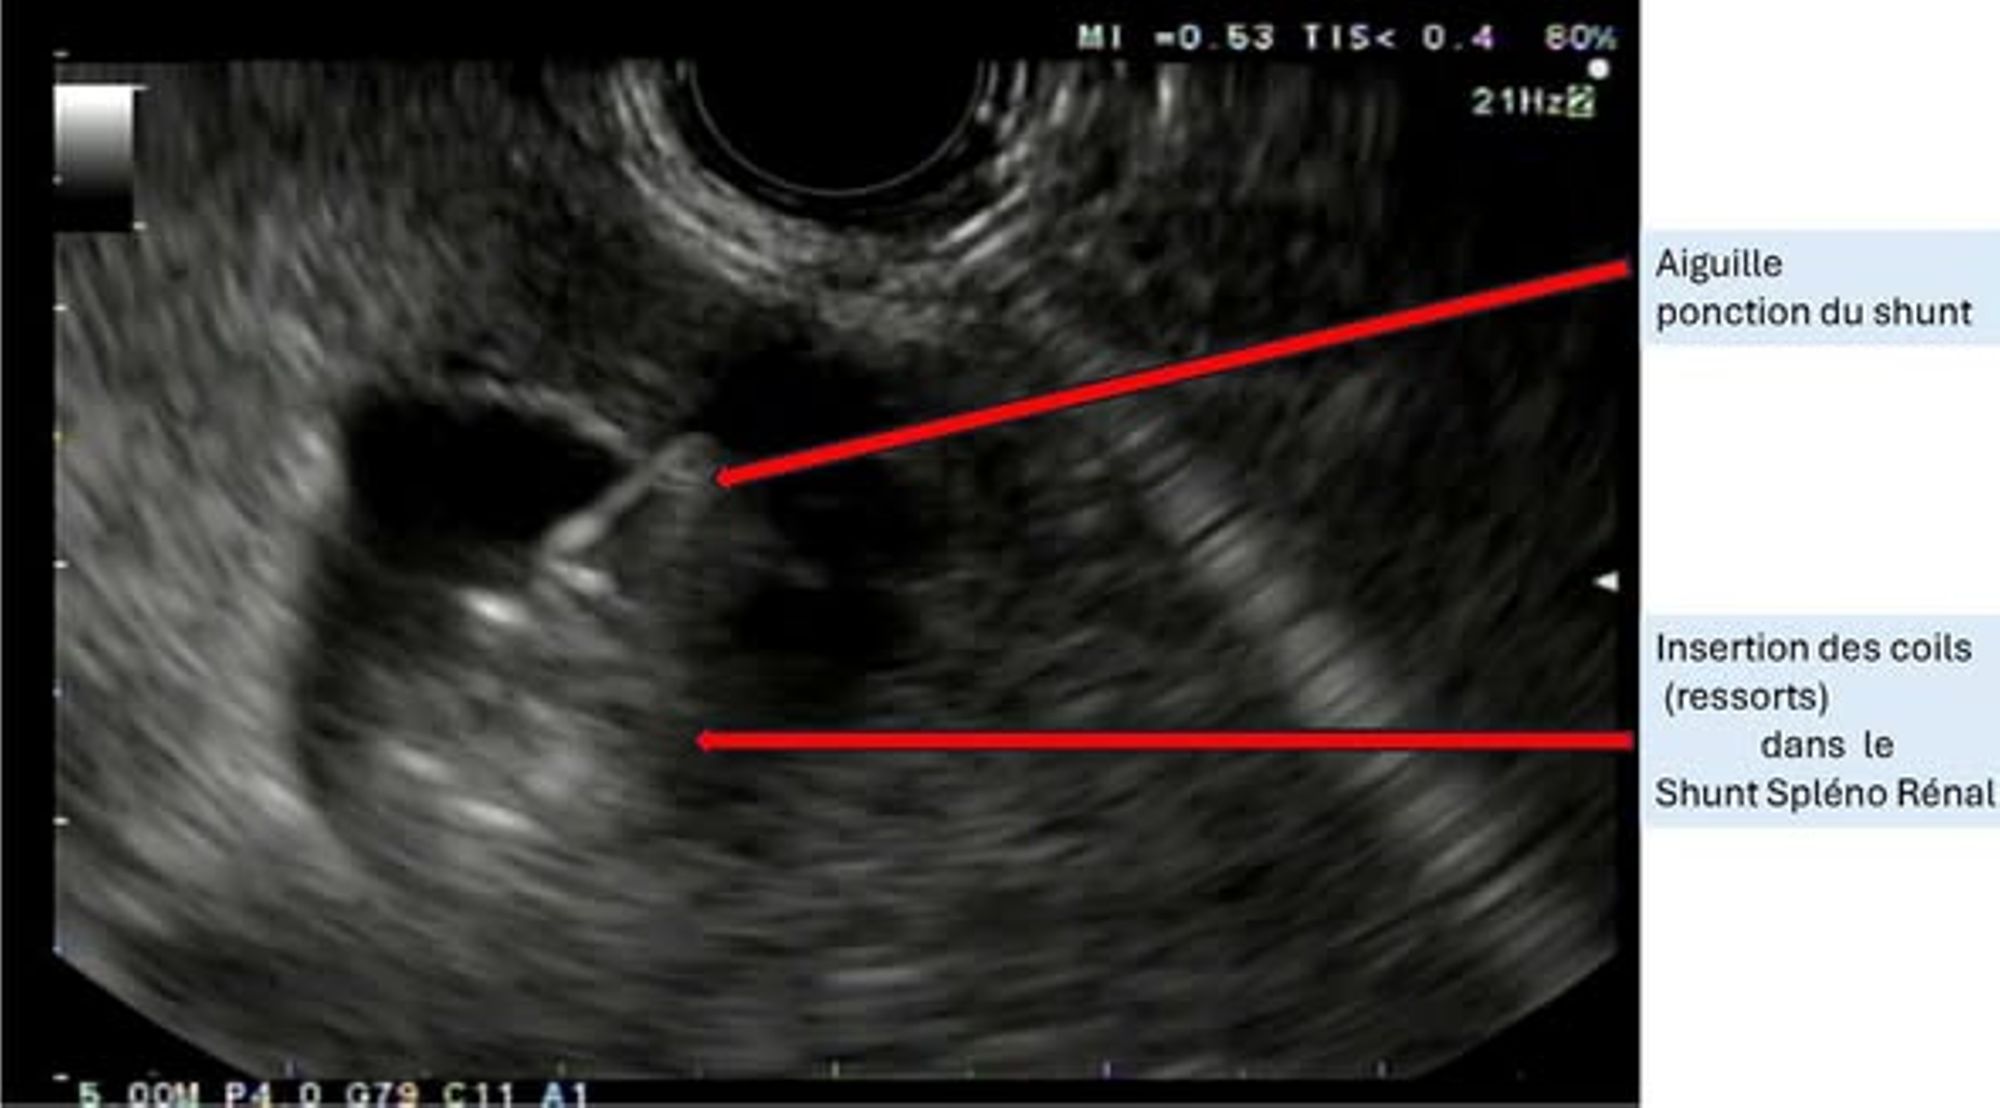

L’intervention a consisté à réaliser une embolisation, au cours d’une endoscopie, des vaisseaux qui court-circuitent l’élimination des substances toxiques chez un patient souffrant d’une maladie grave du foie compliquée d’épisodes répétés et invalidants de cette encéphalopathie hépatique.

Le geste s’est déroulé sans complication, lors d’une écho-endoscopie habituelle, sous anesthésie générale.